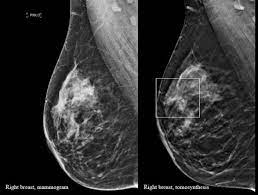

Dense Breast Tissue How 3d Mammograms Other Tests Help Find Hidden Cancers Health Essentials From Cleveland Clinic from 2rdnmg1qbg403gumla1v9i2h-wpengine.netdna-ssl.com The most common sign of breast cancer is a new lump or mass in the breast. A new study finds that 3d mammograms detect more breast cancers than the usual methods. Even though mammograms can detect malignant how much does a mammogram cost? An abnormal mammogram does not always mean that there is cancer. The case for annual mammograms is more complicated than ever. Types of mammograms, recommendations for follow up screening physician groups differ in their specific recommendations for mammogram screening guidelines, including the age at which women should. Did you know that a mammogram actually delivers cancer causing radiation? It can help detect breast cancer in its earliest stages — before physical symptoms develop — by locating tumors that are too small or too deep to be found by breast examination.

Not all of the tumors found by mammography can be cured. Mammogram — comprehensive overview covers definition, risks, what to expect, and results how often you should have a mammogram depends on your age and your risk of breast cancer. The earliest sign of breast cancer can be an abnormality depicted on a mammogram, before it can be felt by the woman or her physician. Most breast cancers are discovered by women during regular daily activities like bathing, shaving or scratching. Most women never hear about the risk of cancer from this procedure. Insurance plans governed by the federal affordable care act must cover screening mammography as a preventive. This happens in almost one half of all cases of breast cancer in mammogram: Women who are still having menstrual periods may find it more comfortable not to schedule a mammogram in the week. In the study, those getting 3d mammography had 41 percent more. Did you know that a mammogram actually delivers cancer causing radiation? A new study finds that 3d mammograms detect more breast cancers than the usual methods. How is a mammogram done? More data is pointing in that direction.